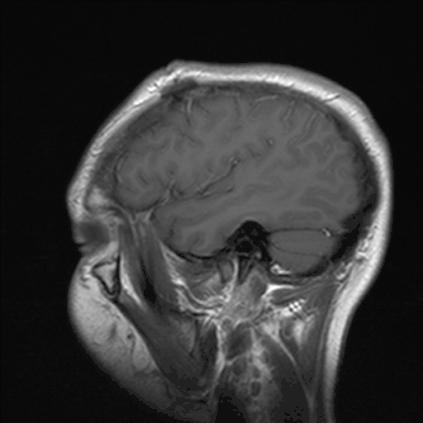

作为法国仁心医院(Hôpital de la Pitié)的首席神经学家,约瑟夫·巴宾斯基(Joseph Babinski)对各种不同寻常的现象早已见怪不怪了。但是,1914年,有两位病人从其中“脱颖而出”,他们的右侧大脑都有损伤,导致他们左半边身体瘫痪(右侧大脑控制左侧身体,左侧大脑控制右侧身体)。

对像巴宾斯基这样经验丰富的神经学家来说,这也没什么。真正让他感到震惊的是,这两位病人都坚称自己好得很,根本没有意识到自己的身体出了问题。在1914年发表在医学期刊上的一篇文章中,巴宾斯基解释道,当他向其中的一位病人推荐使用电击疗法时,那个病人回应说:“你为什么要电击我?我又没瘫痪。”巴宾斯基为描述这种症状创造了一个新词:疾病感缺失(anosognosia),其字面意思是“缺乏认知”。

图源:psychosis

有些病人明知道自己有病却仍会坚称自己没问题,但和这种睁着眼睛说瞎话的情况不同,巴宾斯基相信,他的这两位病人没有撒谎,他们真的没有意识到自己的半边身子瘫痪了,一点儿都没有怀疑。他们大脑中的某些东西——但巴宾斯基不知道究竟是什么——一定损坏了。在接下去的80年里,疾病感缺失这个词完全成了神经科学里的专有词汇,多用来描述生理性的身体状况。直到20世纪90年代中叶,才有一些精神病医师尝试把这个词用在自己的病人身上。这一尝试几乎立刻陷入了反对的浪潮。

最后,巴德雷表示,之所以疾病感缺失会成为精神病学上的一大难题,是因为我们现在还很缺乏这一问题上的神经科学数据。“我觉得现有的证据尚不足以证明精神分裂症必然会导致大脑患上疾病感缺失症。”

也许确实如此,不过它们之间或许仍有关联性。智库精神疾病政策组织的创建者DJ·杰斐(DJ Jaffe)是保障严重精神疾病患者权益的倡导者,他就辩称,各类脑成像数据表明,精神分裂症患者的大脑运作方式和典型的正常大脑颇为不同。